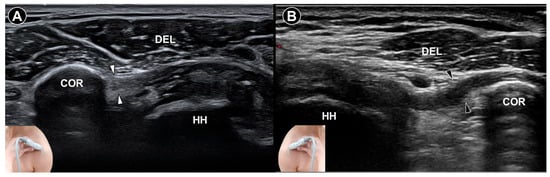

Four characteristic sonographic features were identified: coracohumeral ligament thickening (defined as a threshold of 3.0 mm) (Figure 1), inferior capsule thickening (cutoff values ranging from 2.0 mm to 3.5 mm) (Figure 2), rotator interval abnormalities (hypoechoic soft tissue thickening and/or increased vascularity) (Figure 3), and restriction of the range of motion. Their respective sensitivities were 64.4% (95% CI: 48.8–78.1), 82.1% (95% CI: 73.8–88.7), 82.6% (95% CI: 74.1–89.2), and 94.3% (95% CI: 84.3–98.8), while specificities were 88.9% (95% CI: 76.0–96.3), 95.7% (95% CI: 90.3–98.6), 93.9% (95% CI: 89.8–96.7), and 90.9% (95% CI: 75.7–98.1), respectively. The restriction of the range of motion will be further elaborated in the section on Dynamic Examination. These findings support the incorporation of B-mode ultrasound into routine diagnostic workflows for adhesive capsulitis, particularly in settings where magnetic resonance imaging is less accessible or cost-prohibitive.

Regarding abnormalities in the rotator cuff, Lee et al. [29] exemplified those changes by prospectively investigating 30 individuals clinically diagnosed with adhesive capsulitis and comparing them with two control groups: 10 healthy volunteers and 100 patients with suspected rotator cuff tears. The diagnosis of adhesive capsulitis was based on clinical criteria, including shoulder pain and stiffness lasting more than 15 weeks, increasing severity at rest, and restricted motion greater than 30° in at least two planes. Using both grayscale and color Doppler ultrasound, the researchers assessed the rotator interval. Among the adhesive capsulitis group, 87% (26 patients) exhibited a hypoechoic pattern with increased vascularity in the rotator interval. Three patients showed hypoechoic changes without hypervascularity, while one had normal sonographic findings. Arthroscopic evaluation—performed in all cases—confirmed fibrovascular inflammatory soft-tissue changes in the rotator interval consistent with adhesive capsulitis. In contrast, such sonographic and arthroscopic features were absent in healthy individuals and those with suspected rotator cuff tears.

Figure 3. Ultrasound imaging of the rotator cuff interval (white arrowheads) in a normal shoulder (A). In contrast, the coracohumeral ligament (black arrowheads) in a shoulder with adhesive capsulitis exhibits increased vascularity (B). DEL, deltoid muscle; HH, humeral head; asterisks, long head tendon of the biceps brachii.